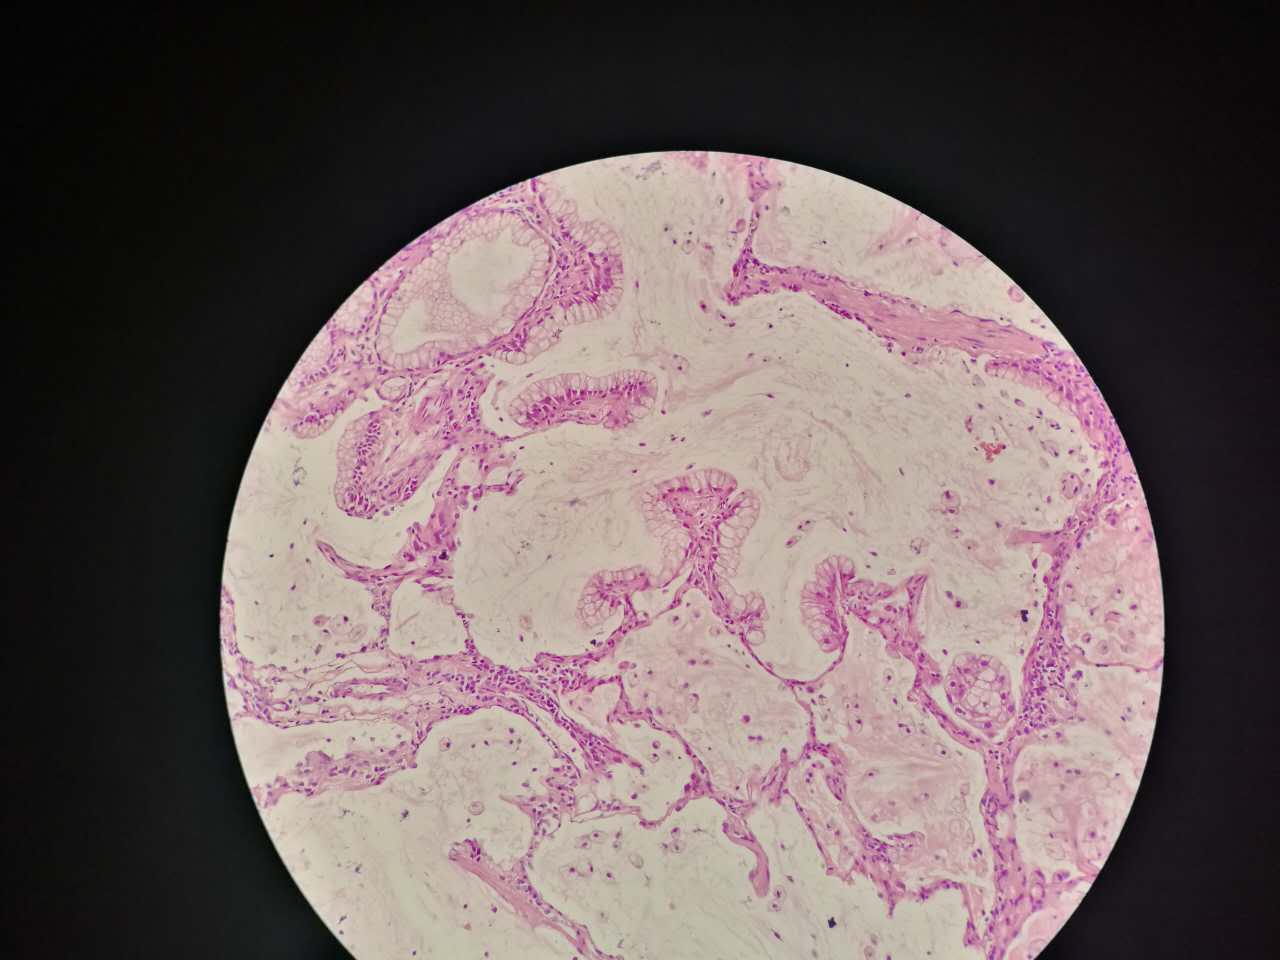

这个是早期结节状的粘液型腺癌

随着粘液近距离播散

早期粘液漂散也是近距离的,右侧肺泡里干净,没粘液,粘液产量有限,并且互相有黏连牵制。

所以结节性粘液腺癌边界一般较清楚

粘液型腺癌的肿瘤细胞排列整齐,核位于基底,细胞呈柱状。

肺泡间隔(间质)经常比较细

差不多都长这样

这个生长密集,相对要重

这个细支气管,一半癌浸润

肿瘤细胞形态仍然相似

中央有个肺血管,说明破坏力不强